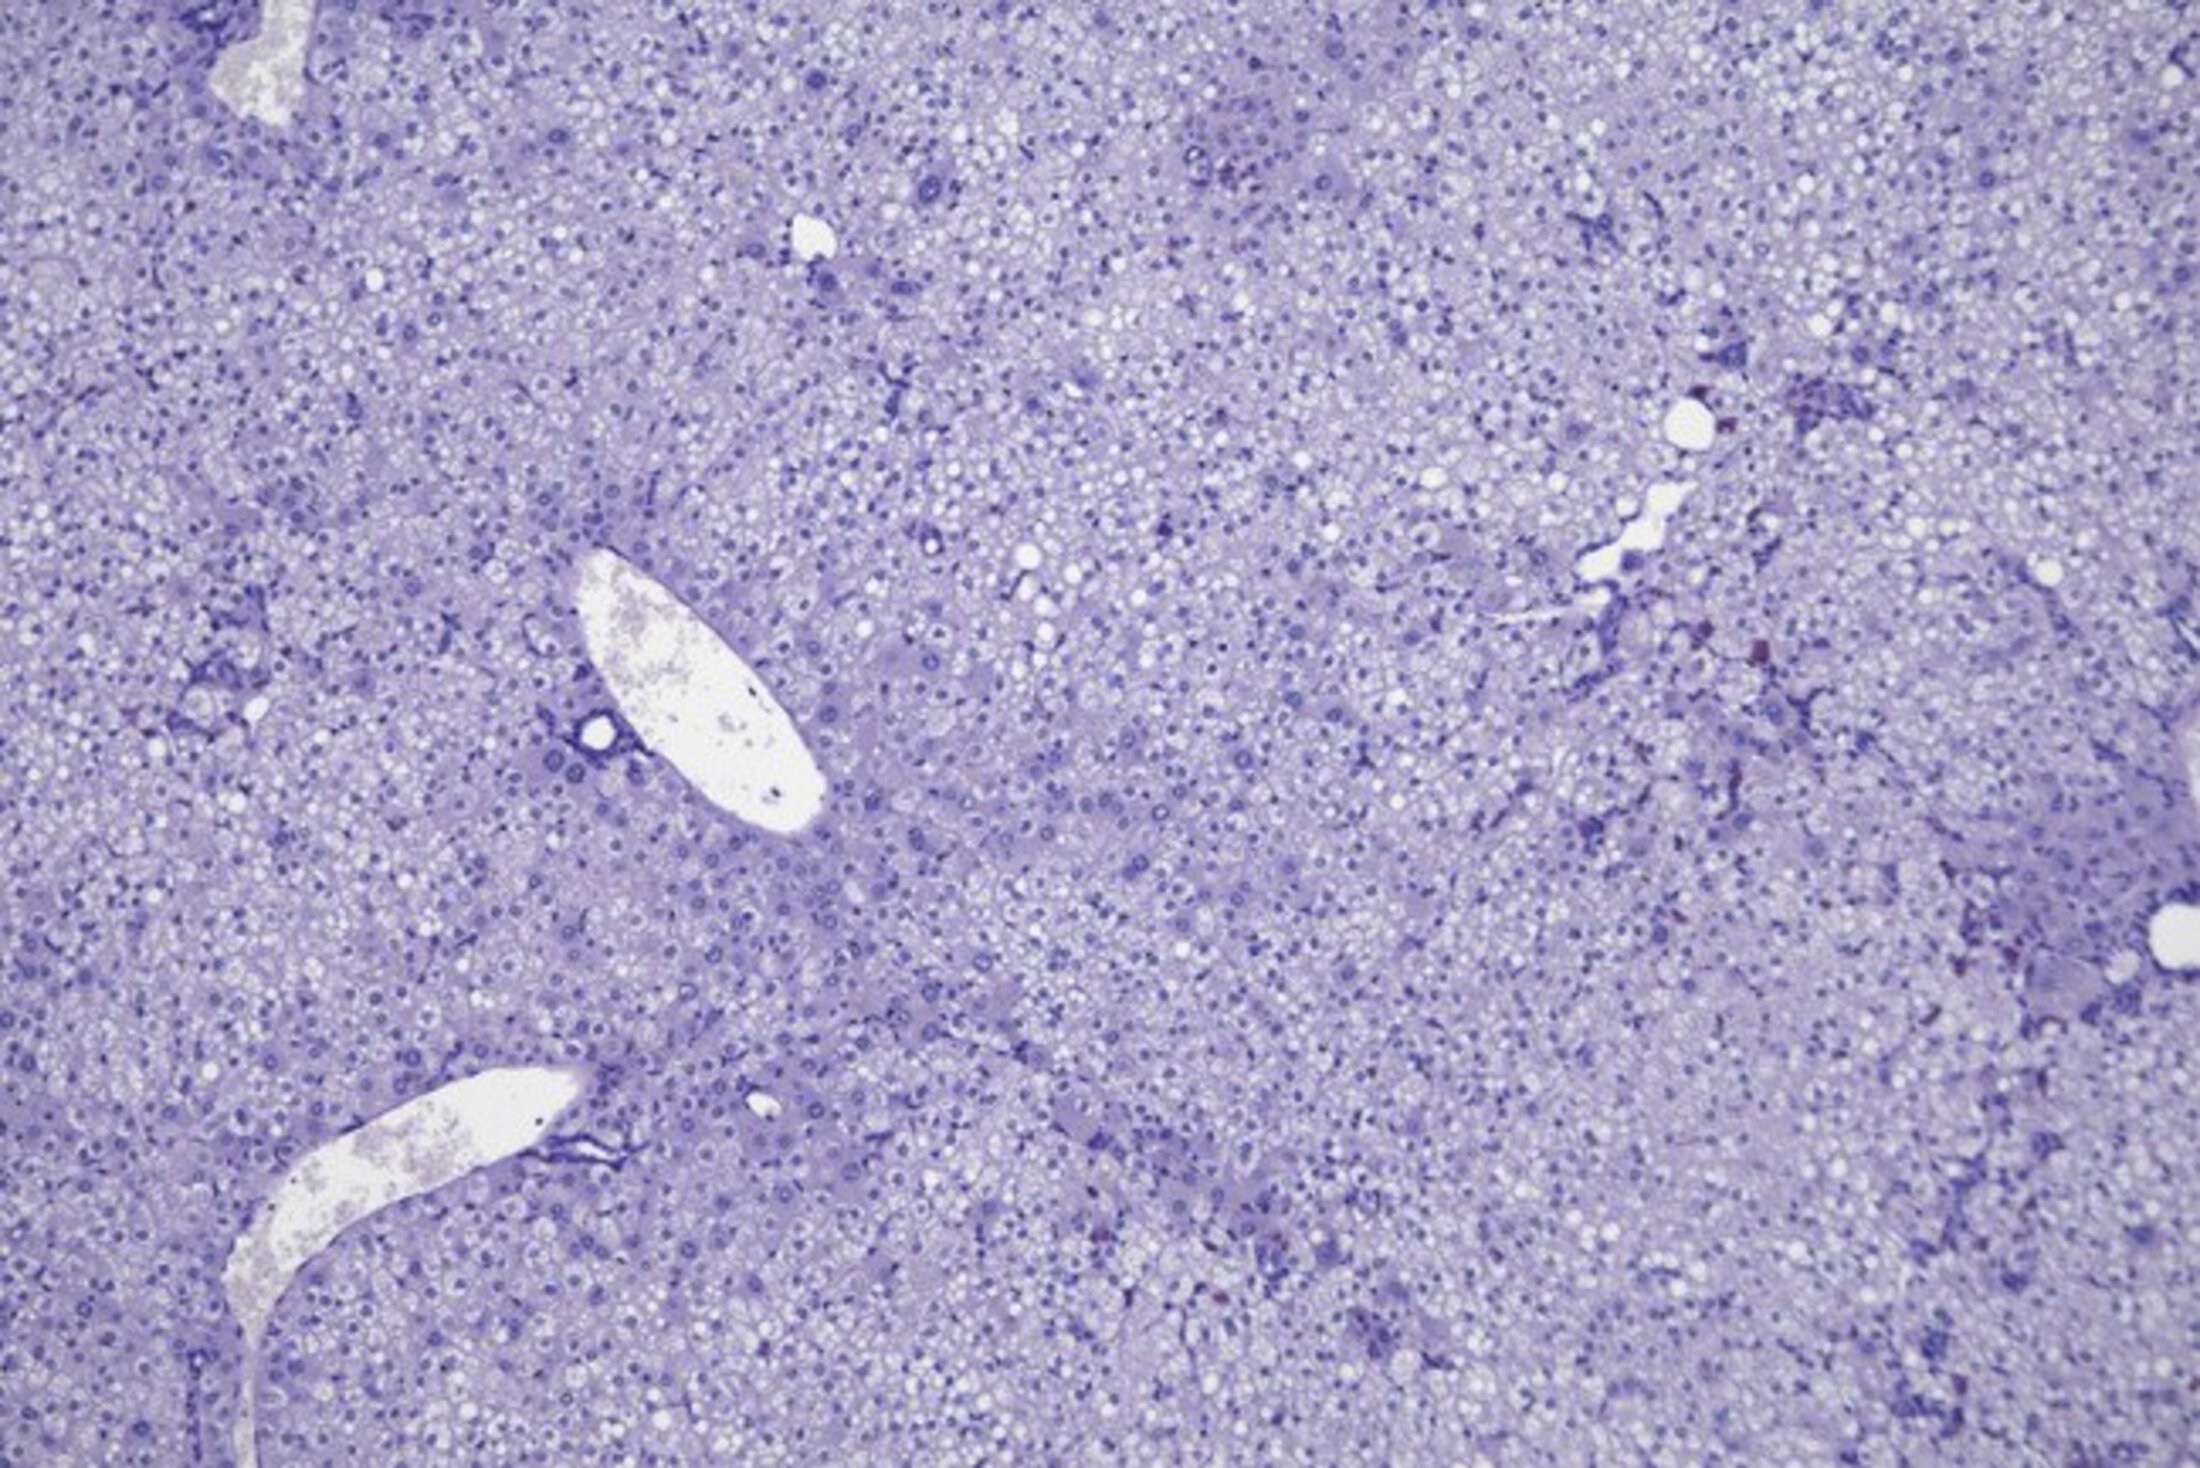

To identify potential new therapeutics, Duncan and his research team – led by Ray (Jui-Tung) Liu, Ph.D., a postdoctoral scholar, and Caren Doueiry, a graduate student, lead authors for this study – created human liver-like cells from induced pluripotent stem cells (iPSCs). iPSCs are artificial stem cells derived from skin cells or blood cells. This technique allowed the team to produce large numbers of cells to screen a large library of chemical compounds. Using this model system, the team found a unique class of compounds that showed promise in treating FH.